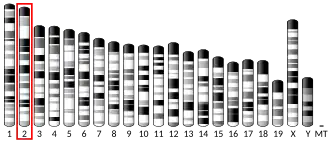

The mutations of the FBN-1 gene at six chromosomal loci, TAAD1 at 5q13-14, FAA1 at 11q23-24, TAAD2 at 3p24-25, TAAD3 at 15q24-26, TAAD4 at 10q23-24 and MYH11 at 16p12-13 are known to be triggers of MFS.[23] These loci tend to have genes that are involved in vascular function.[23] The MYH11 gene is responsible for the smooth muscle myosin heavy chain and ACTA2 at TAAD4 loci encodes for smooth muscle alpha-actin.[23]